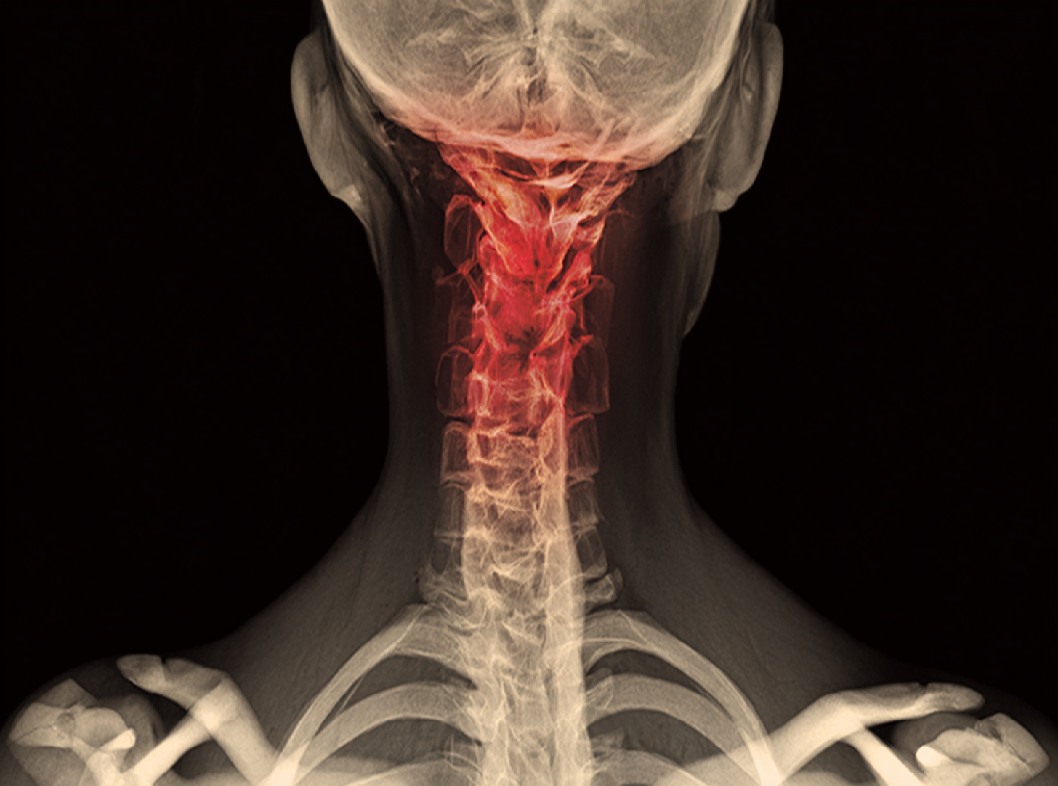

МРТ (магнитно-резонансная томография):

это метод образования изображения, который использует магнитные поля и радиоволны для создания детальных изображений органов и тканей. МРТ может быть полезным для более подробной визуализации гемангиомы и ее окружающих тканей.